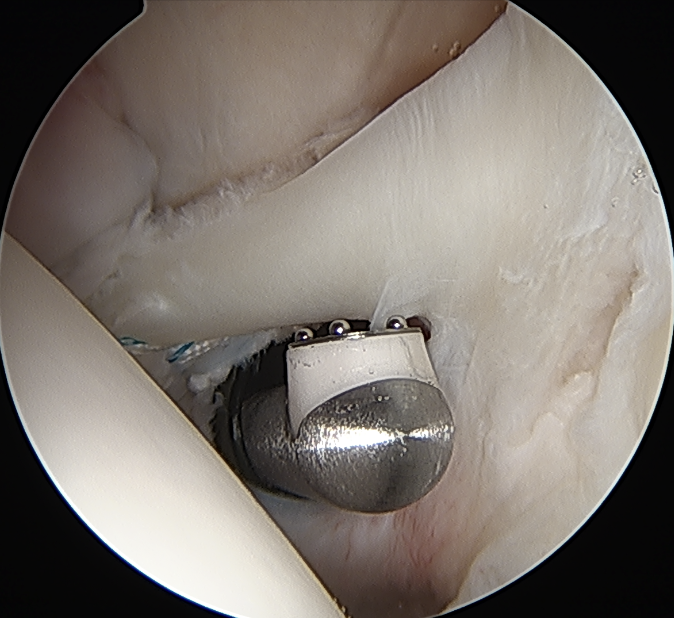

- anchor biceps tendon into bicipital groove

Anchor biceps tendon into bicipital groove